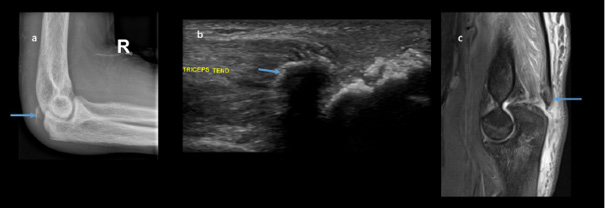

Plain radiographs showed significant bilateral olecranon soft tissue swelling with faint curvilinear ossification proximally suspicious for bilateral avulsion fractures. The ultrasound confirmed loss of tension of the triceps tendon attached to a small bone fragment on the right (Figures 1 and 2). Pelvis radiographs showed an avulsion fracture of the lesser trochanter of the left femur and marked bony sclerosis consistent with renal osteodystrophy. CT of the left elbow indicated a small bony fragment in the distal triceps tendon area with cortical irregularity and significant soft tissue swelling. CT pelvis revealed diffusely increased bone density, subchondral erosions, and resorption at the sacroiliac joints as well as femoral necks consistent with secondary hyperparathyroidism due to end-stage renal disease. MRI of the hip showed generalized skeletal sclerosis along with avulsion of the left iliopsoas tendon with proximal retraction and adjacent soft tissue oedema (Figure 3).

Ultrasound (US) can serve as a complementary modality in assessing associated soft tissue injuries and detecting some occult fractures when radiographs are inconclusive [14,16–18]. However, its role is largely adjunctive, especially in cases where fractures are already evident on radiographs, as was in our case.

In bone imaging, ultrasound visualizes only the cortical surface as a bright (hyperechoic) line, without the ability to assess trabecular architecture [14,23,24]. While ultrasound can occasionally help identify periosteal changes, hematoma, or tendon involvement, definitive diagnosis of avulsion fractures typically relies on radiography, CT, and MRI. In our patient, radiographic and cross-sectional imaging findings were sufficient to confirm the diagnosis, with ultrasound providing supportive but non-essential information.

In our case, the left triceps avulsion fracture was quite obvious, with the loss of elbow extension against gravity with a palpable gap in the tendon. Hence, the left elbow was immobilized in a plaster back slab, and only the right elbow ultrasound scan was performed at the time of presentation. Radiographs, CT, and MRI were helpful in confirming the diagnosis of avulsion fractures and excluding the differential diagnosis of Hydroxyapatite Deposition Disease (HADD) in the tendons, which is also common in patients with renal osteodystrophy.